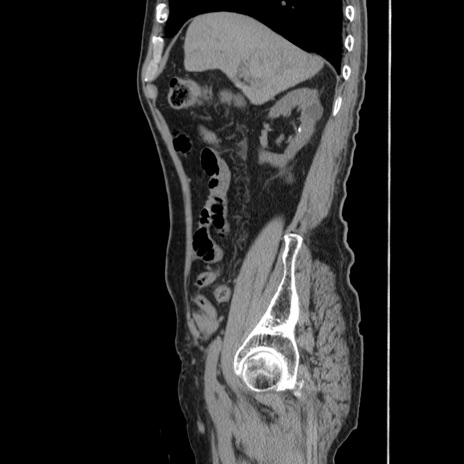

症例24(矢状断像)

【症例】80歳代男性

【主訴】左側腹部痛、嘔吐

【現病歴】本日早朝より左腹部に痛みあり。昼頃嘔吐認めたため、救急要請。

【既往歴】直腸癌(Mile手術)、胆摘

【身体所見】意識清明、BT 35.9℃、BP 221/93mmHg、SpO2 97%(RA) 、腹部:左ストーマ周囲に限局性の腹部膨隆あり。 膨隆部自発痛・圧痛あり・軟。

【データ】WBC 7700、CRP 0.09